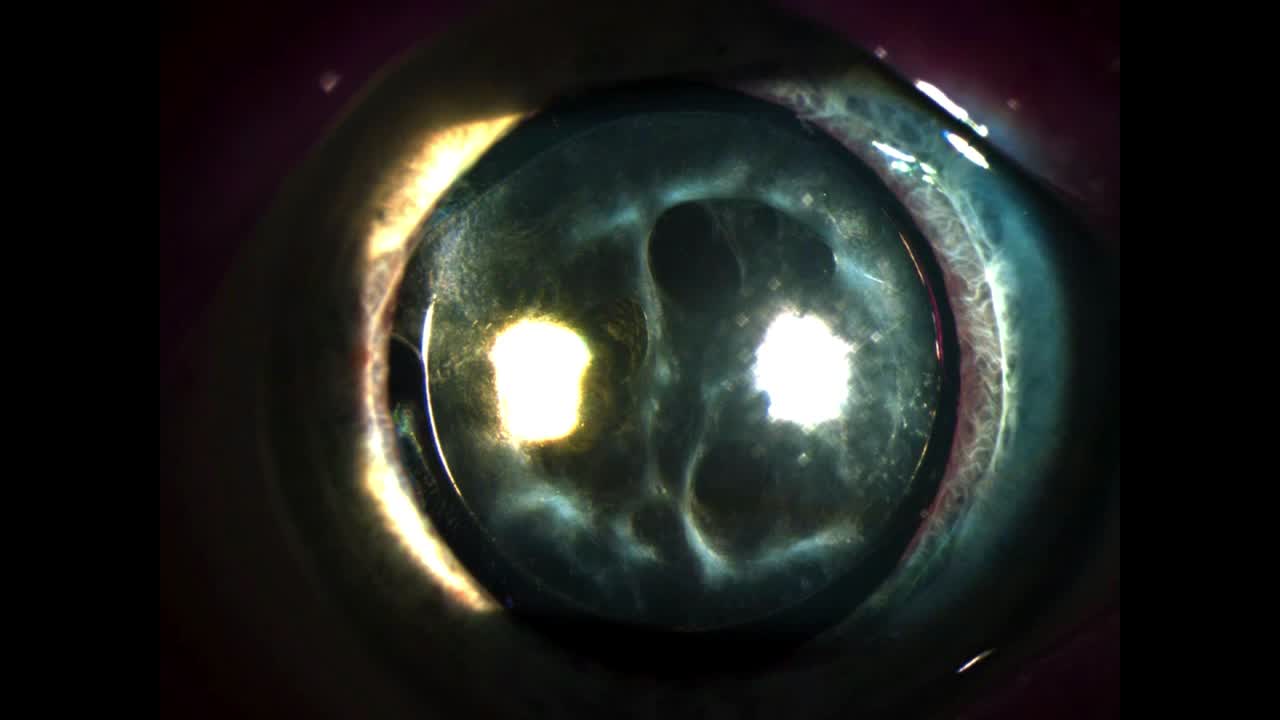

Robert Osher, M.D.